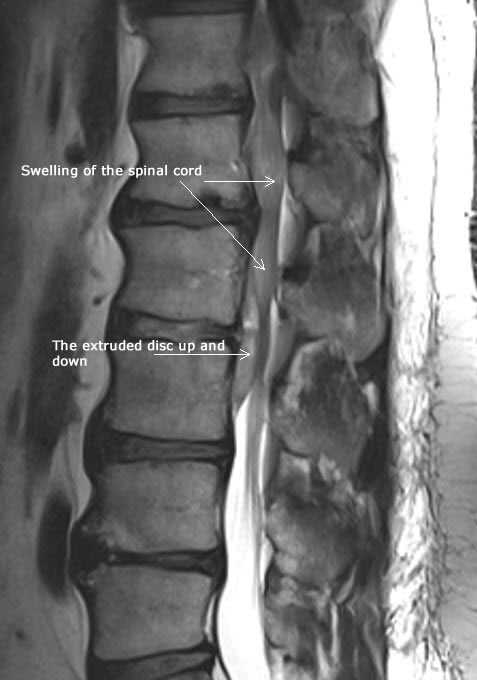

06-APRIL-2025  RAMI UMAR MUHAMED AL-HASHAM  52 YEARS  EXTRUDED DISC L2-3 WITH FAR UP AND DOWNWARD MIGRATION WITH ELEMENTS OF CAUDA EQUINA MORE TO LEFT.

MRI lumbar spine done the same day showing extruded disc L2-3 with far upward, downward migration and left foraminal occlusion.

Fig-1 Preoperative MRI showing the extrusion of L2-3 with swelling of the spinal cord above the surgical lesion.